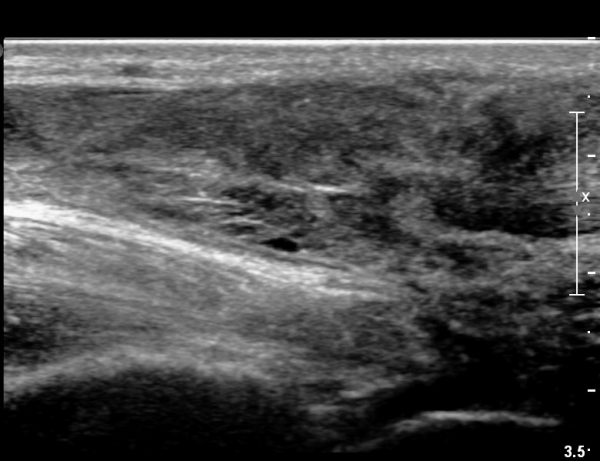

¾ÆÅ³·¹½º°Ç ±ÙÀ§ºÎ Á¾´Ü¸é°Ë»ç¿¡¼­ ¾ÆÅ³·¹½º°ÇÀÇ Àú¿¡ÄÚºÎÁ¾, ±¹¼ÒÀû ¿¬°á¼º ¼Ò½ÇÀÌ °üÂûµÇ¾î

ÆÄ¿­ÀÌ ±¤¹üÀ§ ÇÑ °ÍÀ» º¸¿©ÁÜ(»çÁø 6, 7).

¾ÆÅ³·¹½º°Ç Ⱦ´Ü¸é°Ë»ç¿¡¼­  ¾ÆÅ³·¹½º°ÇÀÇ Àú¿¡ÄÚºÎÁ¾, ±¹¼ÒÀû ¿¬°á¼º ¼Ò½ÇÀÌ °üÂûµÊ(»çÁø 8).